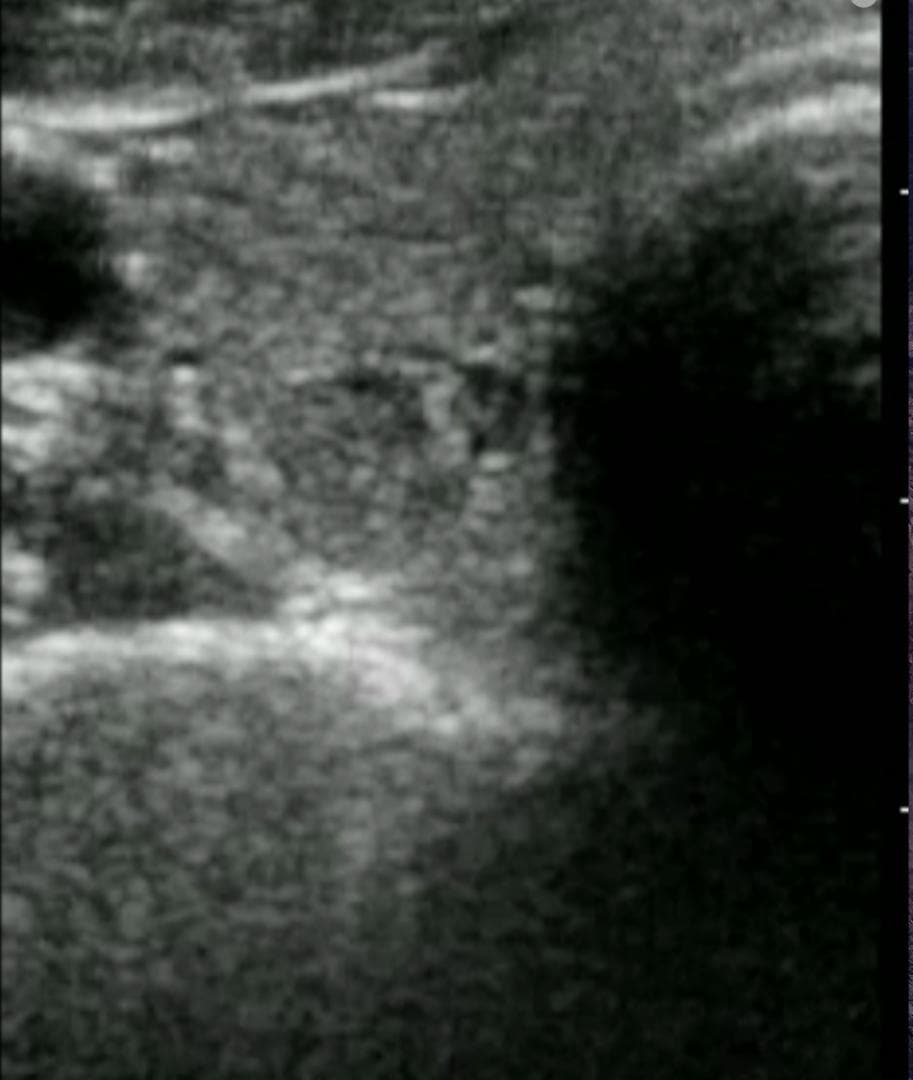

おわかりになる方のみの購入をお願いいたします実際に実施した写真をあげました正常肝臓、胆石症、頸動脈プラーク、同じく頸動脈プラーク、Mrの収縮期、同じくM弁の開放期とA弁の開放期、腹部大動脈瘤、正常の頸動脈、甲状腺右葉の結節、前立腺肥大画像の描出は条件によりますがご検討をお願いいたします経年変化、使用に伴うスレや傷などがあります機能に問題はありませんスキャンは心血管、腹部、体表に対応します外部接続端子のカバーが一部壊れていますが蓋は閉まりますバッテリーはフル充電されますが劣化はあると思います医療用モニタリング機器 Vscan Extend、GE- モデル名: Vscan Extend- ブランド: GE- 色: ホワイト- 機能: 医療用モニタリング機器ご覧いただきありがとうございます。。[新品未使用品]KT TAPE ブラック 25cm プレカット 150枚入